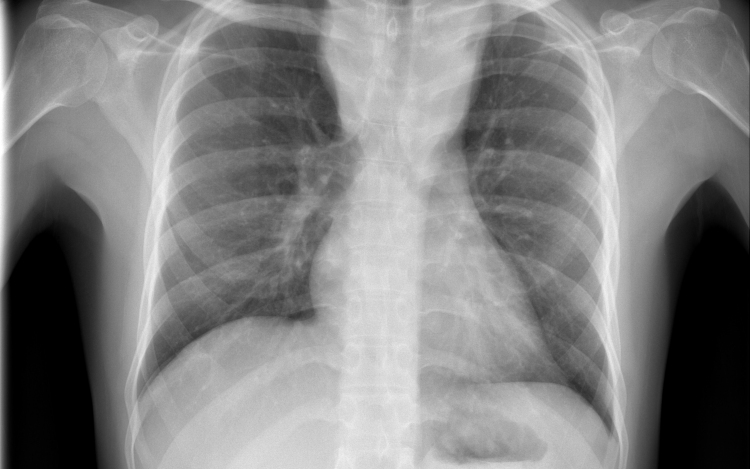

Hétfő reggel óta tbc-tesztet végeznek el a gyerekeken egy szatymazi általános iskolában, ahol egy hete fertőző tüdőbetegségben halt meg egy korábban ott dolgozó nő - közölték az M1 aktuális csatorna déli Híradójában.

A Délmagyar hírportál hétfő reggel írt arról, hogy februárig dolgozott a szatymazi iskolában közmunkásként az nő, aki tuberkulózisban (tbc) halt meg egy hete. Az ügyben rendkívüli szülői értekezletet tartottak. Az általános iskola 260 tanulója közül szülői beleegyezéssel 250-en végzik el a tbc-tesztet.

Felidézték, hogy Magyarországon 1954 óta kötelező a tbc elleni védőoltás. Most az iskola diákjain biztonsági intézkedésként végzik el az úgynevezett Mantoux-tesztet, amely kimutatja, hogy védettek-e a tbc ellen. Ezt a tesztet később, három és hat nap múlva is megismétlik - hangzott el a Híradóban.